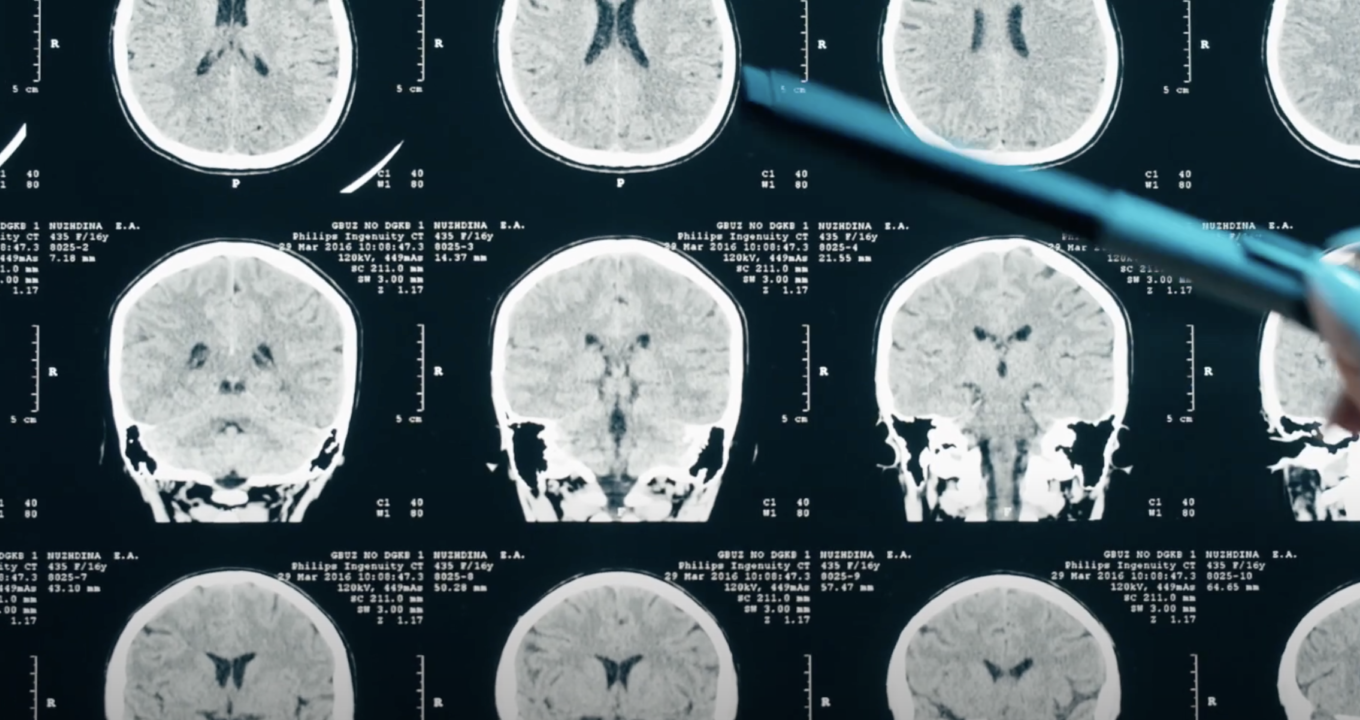

Beyond Symptoms: The Challenge of Detecting Concussion

Standard anatomical imaging often fails to detect these subtle, diffuse changes. Advanced neuroelectric and functional techniques are more effective at identifying the true impact of a concussion.